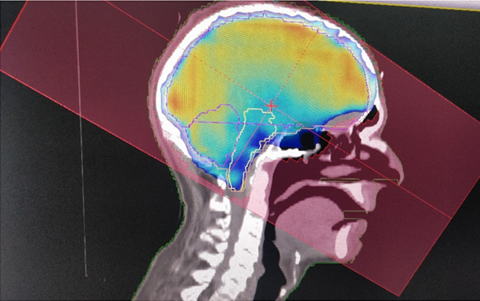

Patient then underwent low anterior resection and received 4 cycles of CAPOX based adjuvant chemotherapy. Patient was then lost to follow up and presented with brain metastasis in June 2021. Patient was then started on decongestive therapy and subjected to whole brain radiotherapy for palliative relief of symptoms.